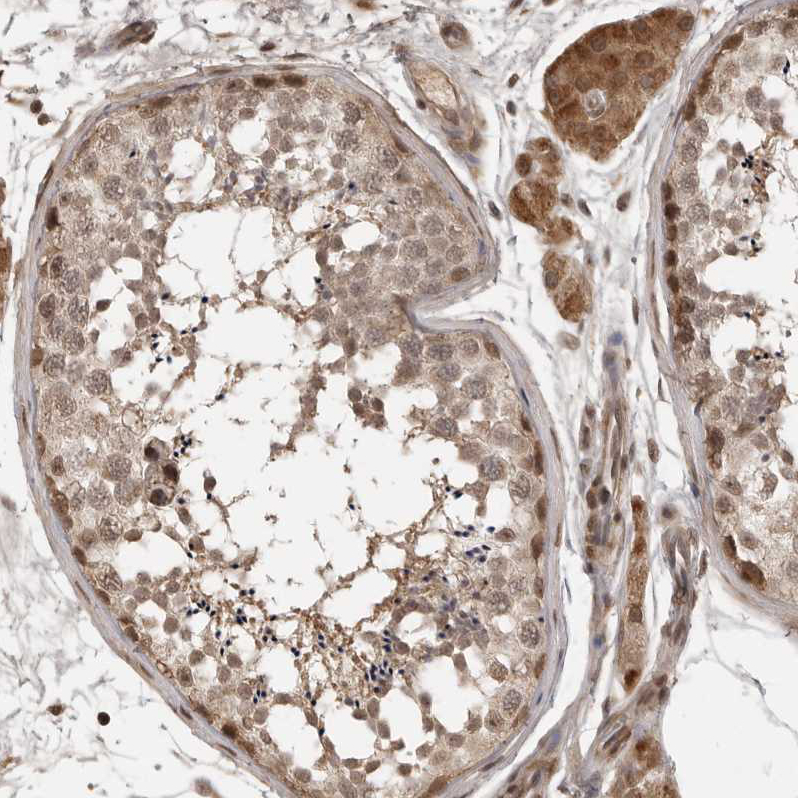

Immunohistochemical staining of human testis shows moderate nuclear and cytoplasmic positivity in cells in seminiferous ducts and Leydig cells.